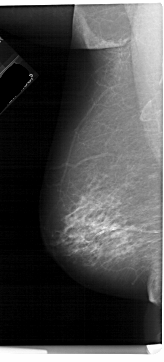

A_1252_1.LEFT_MLO

LEFT_MLO LINES 6871 PIXELS_PER_LINE 3106 BITS_PER_PIXEL 12 RESOLUTION 43.5 NON_OVERLAY